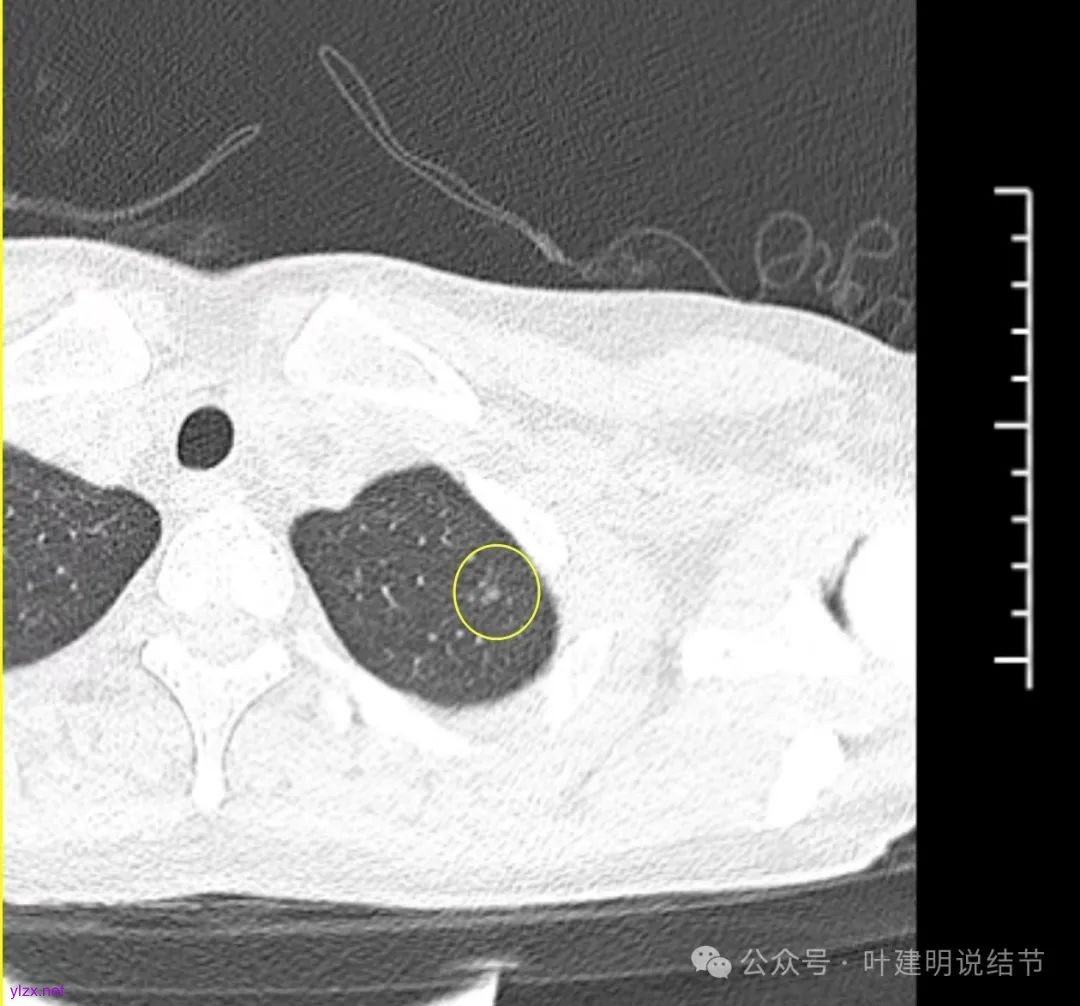

怎么有个点状密度较高的结节在?与上面那截图的淡磨并不完全在一块的。

密度甚高,边界与轮廓清楚,只看这真的不像恶性些。

边缘区也瘤肺界限稍糊,整体轮廓还行。有进展的是不是就是淡磨那处?